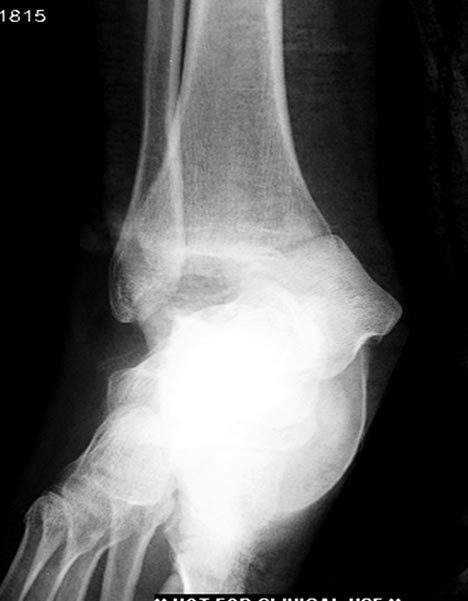

6 день госпитализации-операция на таранной кости.

----------- следущая часть -----------

Вложение не в текстовом формате было извлечено…

Имя     : Picture15.jpg

Тип     : image/jpeg

Размер  : 37494 байтов

Описание: отсутствует

Url     : http://weborto.net:8080/pipermail/ortho/attachments/20180416/07265245/attachment-0002.jpg